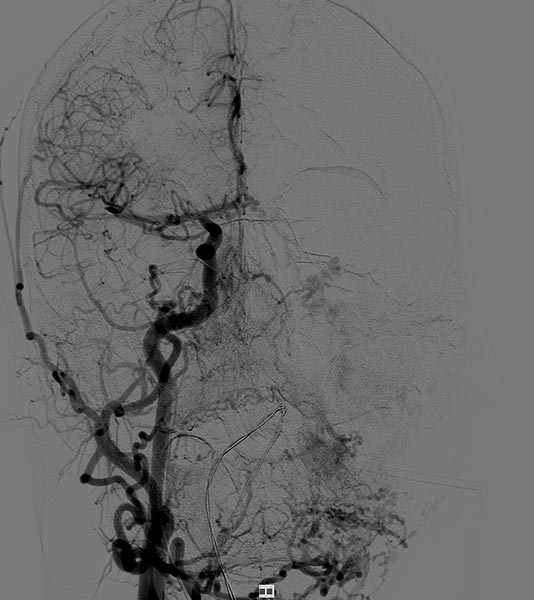

Laterale Ansicht einer digitalen Subtraktionsangiographie nach Injektion in die linke Arteria carotis externa. Die AVM ist als diffuser, netzartiger Nidus mit direktem, starken venösen Abstrom zentral in der linken Wange erkennbar (Fast-flow-Malformation).

Laterale Ansicht, DSA nach Anspritzen der linken Arteria carotis interna. Auch aus der Arteria carotis interna erfolgt eine massive Versorgung des Nidus der AVM, vor allem über die Arteria ophthalmica und den Truncus meningohypophysealis.

Dies erschwert die Embolisationstherapie erheblich.

DSA, anterior-posteriore Ansicht, nach Anspritzen der rechten A. carotis communis. Auch aus der kontralateralen rechten A. carotis externa und A. facialis rechts wird der Nidus der AVM an der linken Wange gespeist.